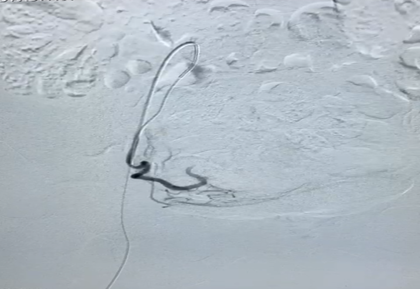

A urine pregnancy test turned out to be negative. On sonographic evaluation, the uterus was 5.4cmX5.1cmX7.3cm (mildly bulky) with heterogeneous echotexture with echogenic areas measuring 2.1cm X 1.87cm X cm2.1 cm with few anechoic areas within and increased vascularity (PSV: 64 cm/sec) within the myometrium which extended into the endometrial cavity. Multiple dilated veins were seen in bilateral adnexa. This led to a differential of uterus arteriovenous malformation (AVM) versus grade 3 retained products of conceptus (RPOC). Considering the high PSV and the type of vascular flow within the myometrium, the diagnosis was more inclined towards AVM (Figure 1).

Figure 1 Doppler flow showing increased vascularity within the uterine AVM.